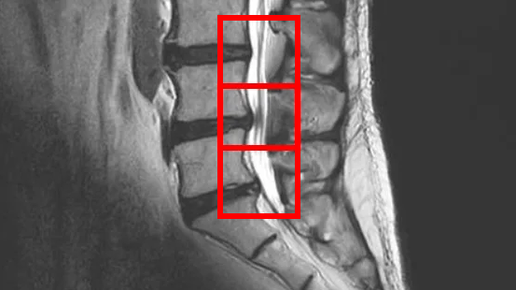

С согласия пациентов публикуем их истории. Пациент – мужчина, 60 лет Лечение в ноябре 2023 года. В июле 2023 года появились боли в пояснице и левой ноге. Принимал обезболивающие препараты, делал вытяжение позвоночника, но боли не проходили. По данным МРТ и результатам осмотра пациента выявлена дегенерация межпозвоночных дисков L3/L4, L4/L5, L5/S1, а также стеноз позвоночного канала L4/L5 и стеноз межпозвонковых отверстий L5/S1. Симптомы по 10-балльной шкале (0 – отсутствие симптомов, 10 – сильны